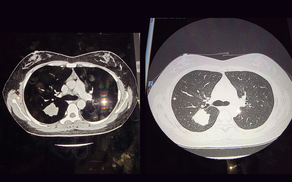

Bệnh viện Đa khoa Quốc tế Nam Sài Gòn đẩy mạnh ứng dụng AI trong chẩn đoán hình ảnh

Trước xu thế nâng cao chất lượng điều trị, nhiều bệnh viện đang tăng tốc đưa trí tuệ nhân tạo (AI) vào thực hành lâm sàng. Bắt nhịp xu hướng này, Bệnh viện Đa khoa Quốc tế Nam Sài Gòn không ngừng đầu tư, cập nhật các giải pháp AI trong chẩn đoán hình ảnh, giúp nâng cao độ chính xác trong chẩn đoán và tối ưu hiệu quả điều trị.